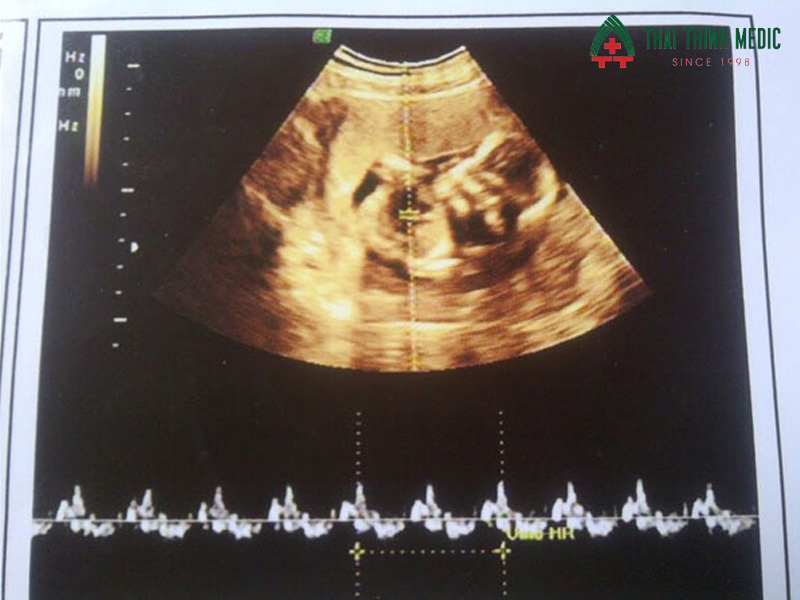

Đo nhịp tim thai

Nhịp tim thai là chỉ số phản ánh sự phát triển tim mạch và sinh lý của thai nhi. Ở tuần 12, nhịp tim thường từ 110–160 nhịp/phút. Bác sĩ sẽ theo dõi nhịp tim để phát hiện các dấu hiệu bất thường như nhịp tim quá chậm hoặc quá nhanh, có thể liên quan đến các vấn đề tim bẩm sinh hoặc tình trạng sức khỏe của mẹ.